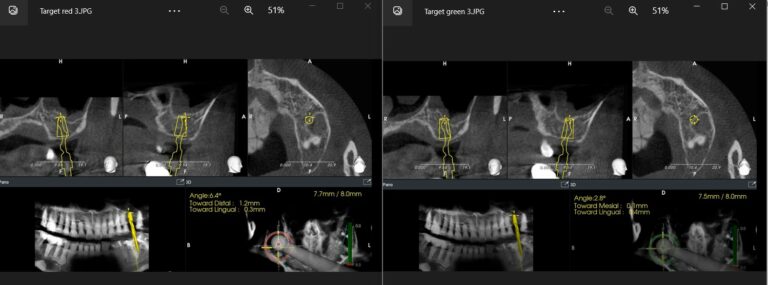

To the left, the implant drill is almost in it’s final depth (7.7/8 mm) yet the angle deviation is at 6.4 degrees. Seeing the red indicator in the navigation system, the operator can now correct the angle accordingly, until the indicator turns green (right side, angle corrected to 2.8 degrees)

Correcting the angle is actually a very important parametre. In reality there are only two main parametres in 3-dimensional deviation of the implant position: platform and angle. We also measure the deviation at apex, but  in reality this is a surrogate of angle deviation: It amplifies the deviation at platform by the implant length. The bigger the angle deviation and the longer the implant, the bigger the apex deviation would be. But for 0 degree angle deviation, the  apex deviation will be exactly as much as the one in the platform and this is elementary geometry.

there are only two parametres in 3-dimensional deviation : platform and angle. Deviation at apex is just a surrogate of angle deviation.